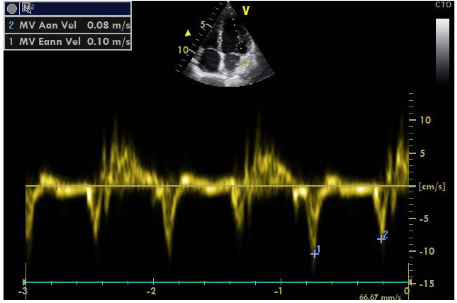

An additional element is the localization of the stenosis in the initial part of renal vessel, as opposed to FMD that commonly affects the middle and peripheral portions. The sudden deterioration of renal function within a short period of time also advocates for atherosclerosis as the FMD has a slower course. It is noted that atherosclerosis may lead to complete abstraction/thrombosis over time, rarely occurring FMD. Finally, the immunological test performed to rule out vasculitis was negative. Renal arteriography indicated a 99% stenosis to the left and the patient underwent a successful stent implantation. After angioplasty, blood pressure returned to normal and the patient did not receive any medication. It is worth noting that despite the presence of stage III hypertension and the underlying disease, the patient did not show signs of diastolic dysfunction in the Doppler (Figures 8–10), nor any signs of hypertrophic left ventricle in ECG.  Not a patient with long-standing uncontrolled hypertension. Moreover, to stress echocardiography with doboutamine there were no wall motion abnormalities, while coronary flow reserve was normal (CFR LAD=2.2) (Figure 11A & 11B).

Figure  8 Tissue Doppler of mitral annulus.